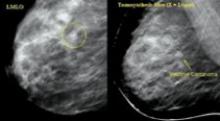

August 31, 2007 — Orthocrat Ltd., a leader in digital imaging software for orthopedic surgeons, has been invited to demonstrate its TraumaCad 2.0 digital surgical planning and templating solution at the prestigious Baltimore Limb Deformity Course, Sept. 1-5 at the Marriott Waterfront Hotel in Baltimore.

Orthocrat will provide hands-on computer-lab demonstrations of its forthcoming TraumaCad 2.0 enhancements during course presentations and individually for physicians in attendance.